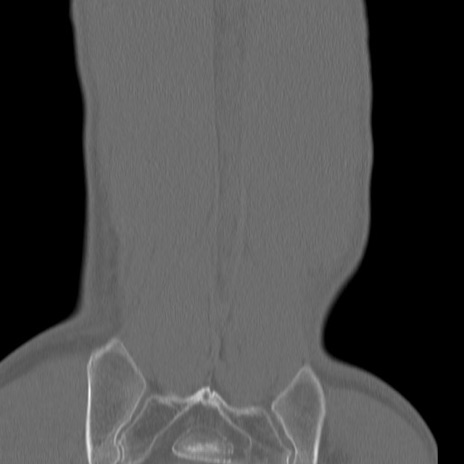

腰椎CT

矢状断像